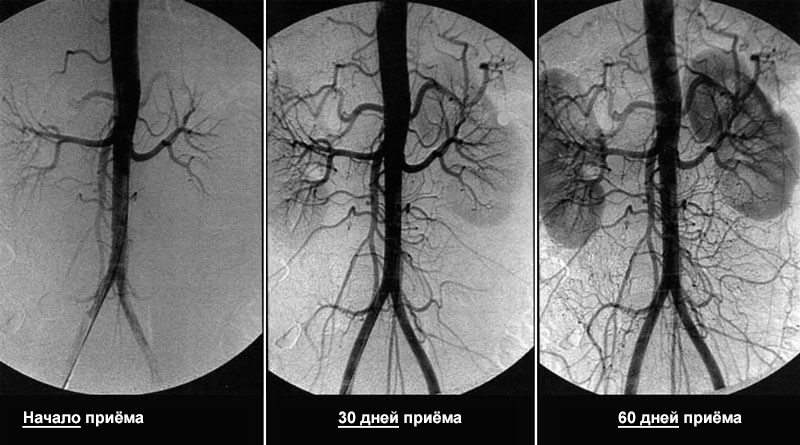

За 1,5 месяца приёма Кордис кровообращение восстанавливается на 99,71%

При этом кровообращение восстанавливается системно – во всех сосудах, артериях и капиллярах.

1. Выводит отложения из сосудов

Растворяет атеросклеротические бляшки, кровяные тромбы и кальциевую известь. Увеличивает просвет сосудов до 99,71% от нормы и восстанавливает кровообращение.